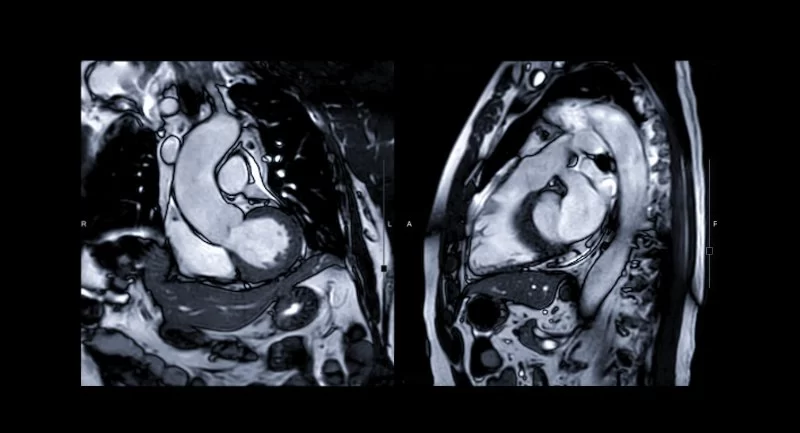

Cardiac MRI, or Magnetic Resonance Imaging, is a diagnostic imaging technique used to get detailed images of the heart and its blood vessels. Unlike traditional imaging methods such as X-rays or CT scans, Cardiac MRI uses magnetic fields and radio waves to create detailed pictures of the heart. This allows doctors to assess the heart’s structure, function, and the surrounding tissues in a way that’s impossible with other techniques.

One of the key advantages of a Cardiac MRI is its ability to visualize soft tissues without the need for radiation, making it a safer option for repeated use. It also provides better clarity and detail, making it especially useful for detecting heart abnormalities that may not show up in other imaging tests.